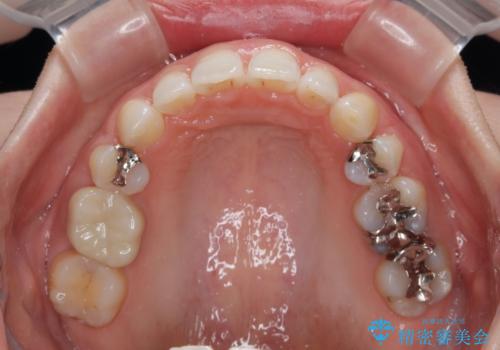

- 口元の突出感と口の閉じにくさを気にして来院された患者様です。

上下左右第一小臼歯4本を抜歯し、ワイヤー装置にて口元を引っ込めるよう矯正治療を行うこととしました。

奥歯が前方に傾斜していることで深く咬みこむ(ディープバイト)状態であったので、なかなか抜歯したスペースが閉じず、様々な方法でディープバイトを改善しながら治療を進めていくこととなりました。